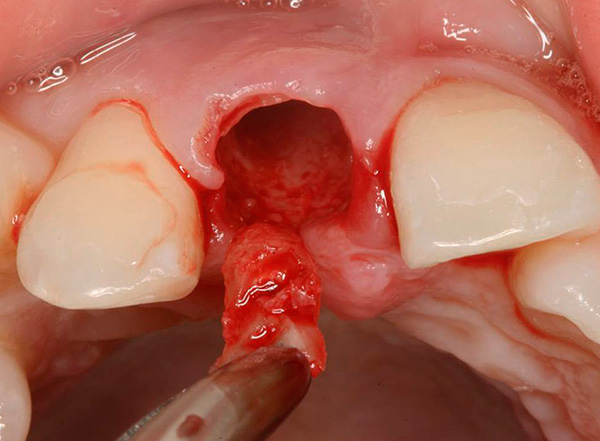

Le fotografie seguenti mostrano l'estrazione del dente, la cui parte della corona viene distrutta quasi al livello delle gengive: